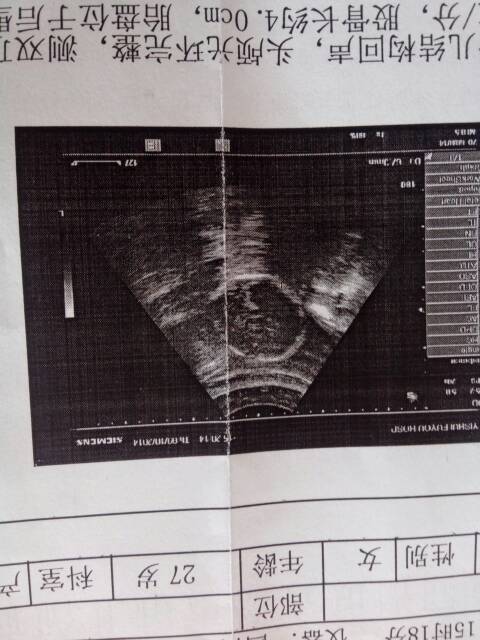

请医生解答,图中有个圆圈,圆圈是宝宝的哪个部位啊?还是羊水啊?还有六个月双顶径6.5,宝宝的头大吗 请医生解答,图中有个圆圈,圆圈是宝宝的哪个部位啊?还是羊水啊?还有六个月双顶径6.5,宝宝的头大吗?谢谢 点击展开 胖娃宁宁 2016-03-17 15:41 为您推荐: 其他回答 根据描述,图中的圆圈就是胎头,即胎头颅骨的显影,用来测量双顶径值。另外,孕6月双顶径6.5cm在正常范围内。 wzlzx520 2016-03-17 18:53 相关问题 孕37加6,双顶径8 7股骨7 4,羊水指数6cm,医生说偏少!要剖!现在已入盆,宝宝会小吗?能知 急…医生说宝宝腹围小,羊水少 该怎么补啊?各位宝妈医生帮帮忙 今天拍的四维图,偏大偏小,属正常么,羊水正常吗,看不懂现在六个月,医生说宝宝坐着的,如果想顺生该